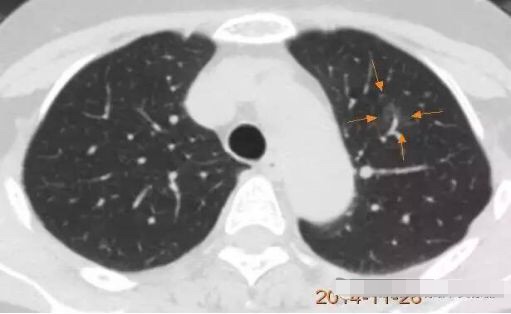

病例2

随访3年,GGO直径基本没有变化

2013年12月

2014年7月

2015年5月

2016年10月